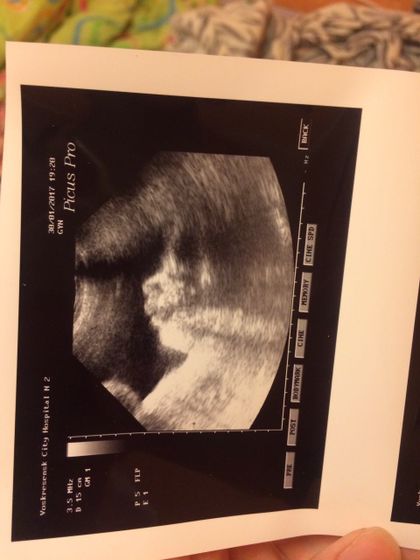

Вчера были на УЗИ! По месячным 33,2 срок, а по узи 34) весим около 2300, врач сказал, что мальчуган волосатый) плацента 1степени зрелости, лежим правильно, обвития нет и все в общем хорошо, а я так переживала!